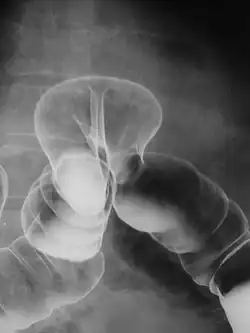

Uma hérnia de hiato é uma variante específica desse tipo, na qual a passagem normal pela qual o esôfago encontra o estômago (hiato esofágico) serve como um "defeito" funcional, permitindo que parte do estômago (periodicamente) "hérnia" no peito. As hérnias de hiato podem ser "deslizantes", nas quais a própria junção gastroesofágica desliza através do defeito para o tórax, ou não deslizantes (também conhecido como para-esofágico), caso em que a junção permanece fixa enquanto outra porção do estômago se move através do defeito. Hérnias não deslizantes ou para-esofágicas podem ser perigosas, pois podem permitir que o estômago gire e obstrua. O reparo é geralmente recomendado.